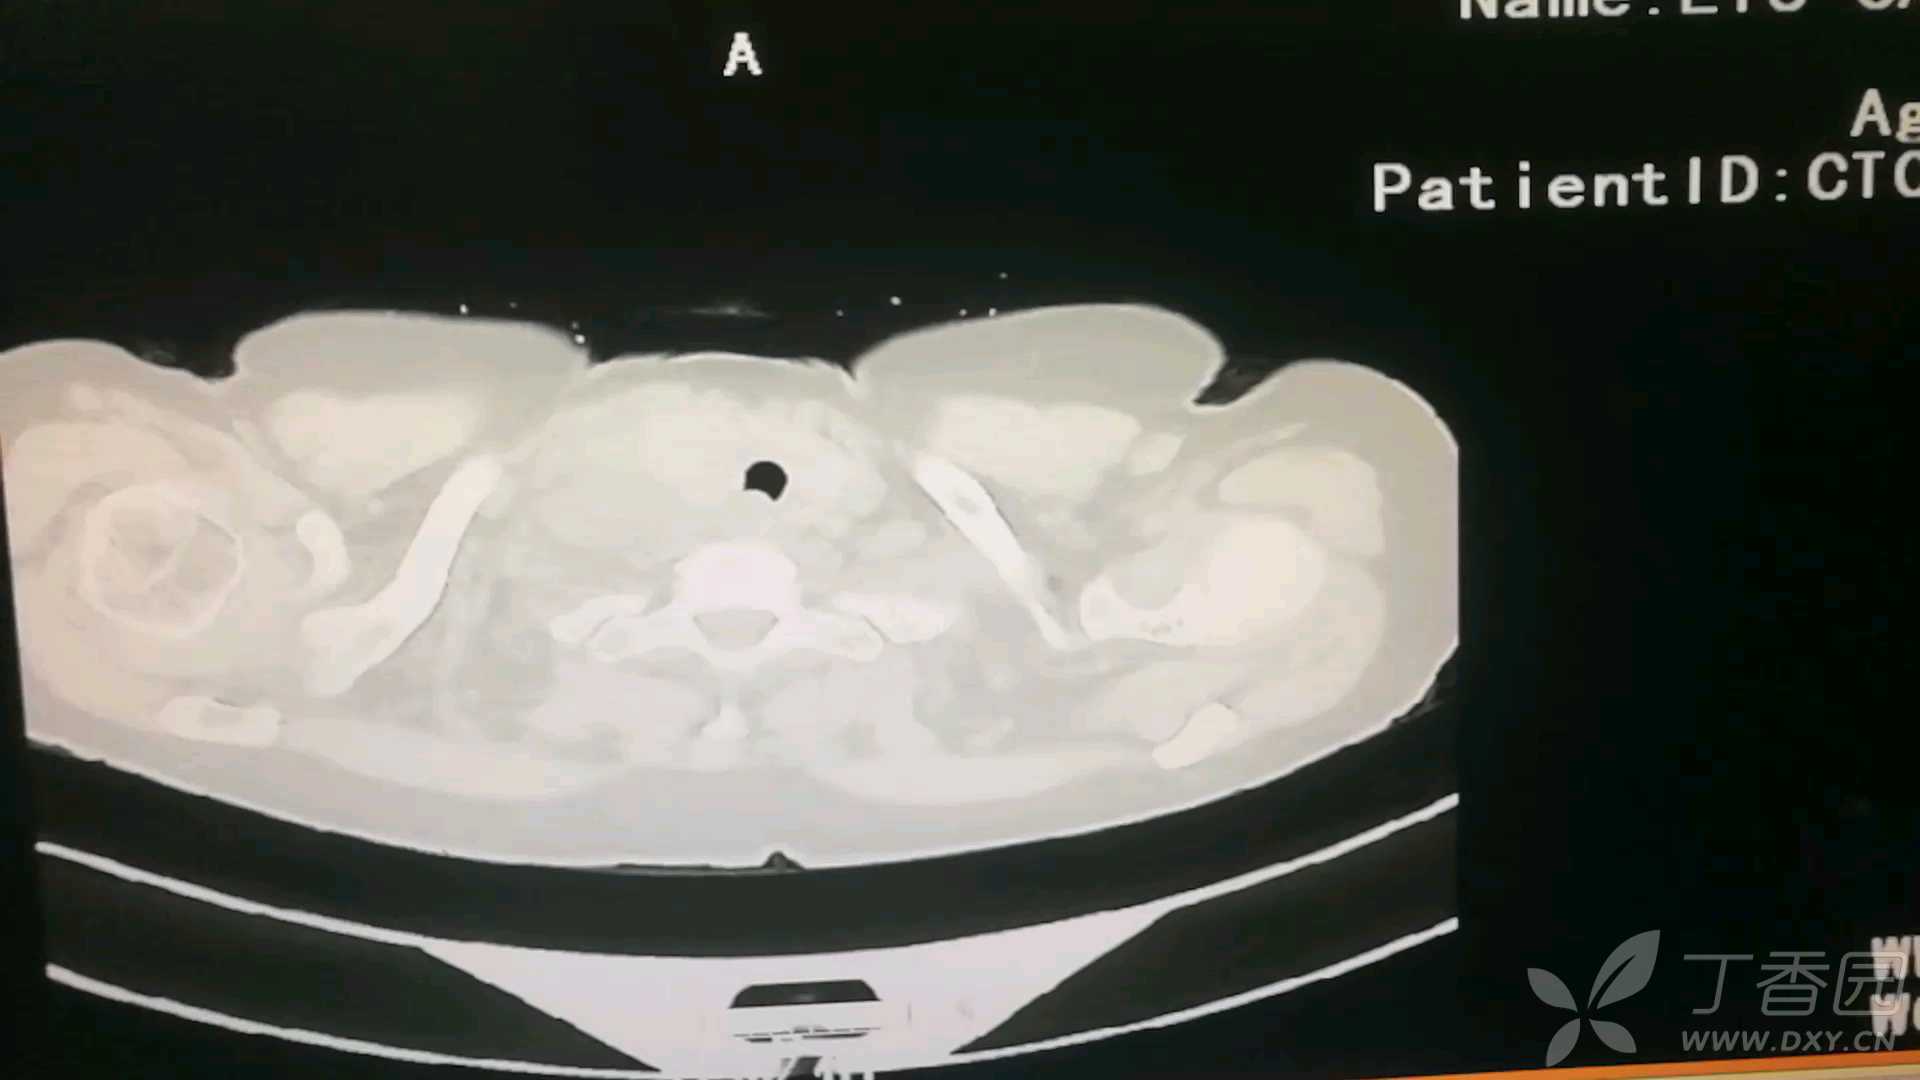

胸部CT: